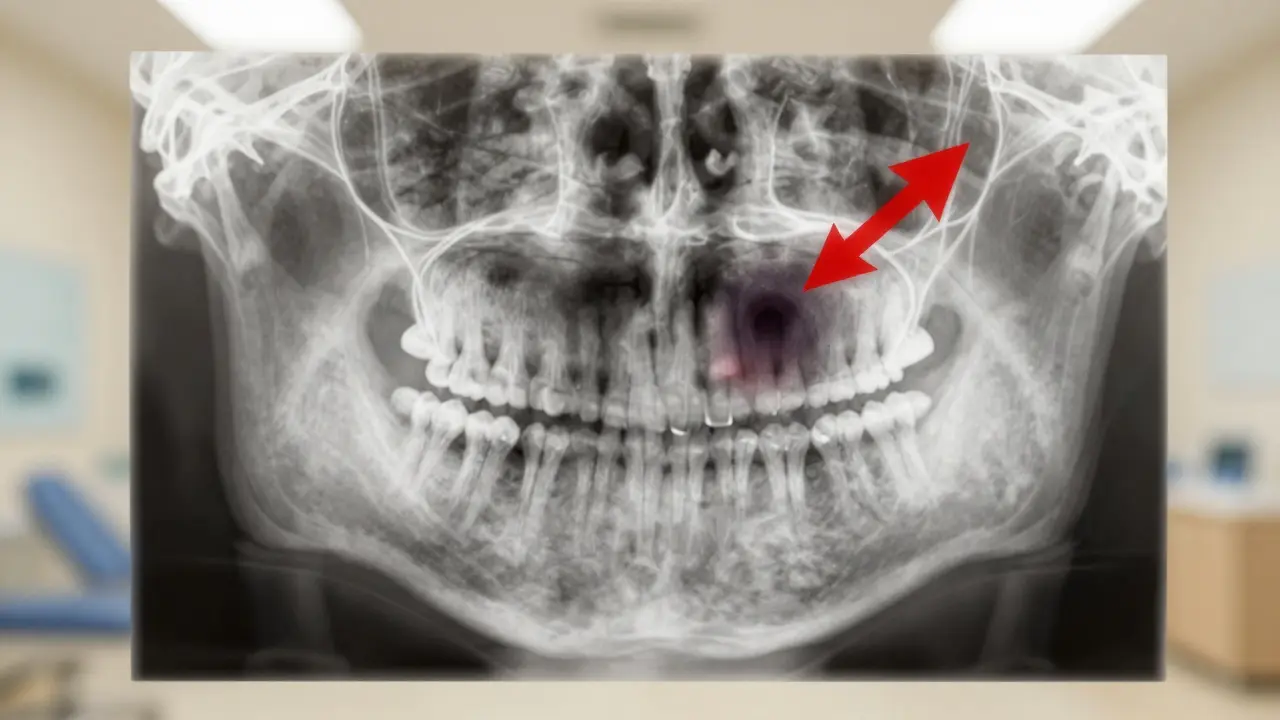

Rentgen čelisti s ukázkou infekce v kořeni zubu

Když přijdete na ordinaci, lékař nejprve udělá rentgen. To ukáže, jak hluboko je infekce a zda je poškozen kořen. Pak může zvolit jednu z těchto možností: